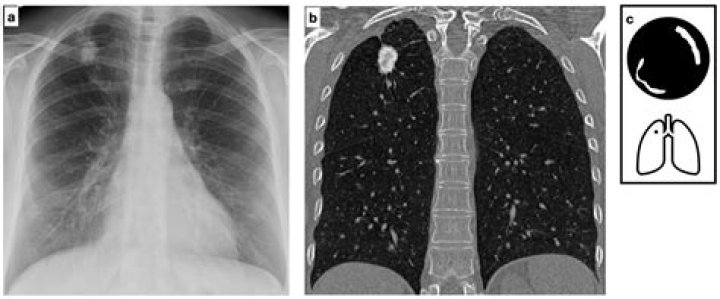

Lung nodules are usually about 0.2 inch (5 millimeters) to 1.2 inches (30 millimeters) in size. A larger lung nodule, such as one that's 30 millimete...